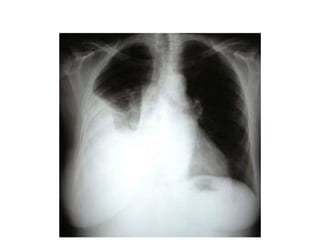

Neumotorax

• Presencia de aire en la cavidad pleural, se clasifica en

espontaneo, iatrogenico y traumatico

Diagnostico

• Se establece por la clinica sugestiva y la rx del torax

que presenta una zona hiperlucida, sin trama

pulmonar y limitado por la linea pleural en su borde

interno